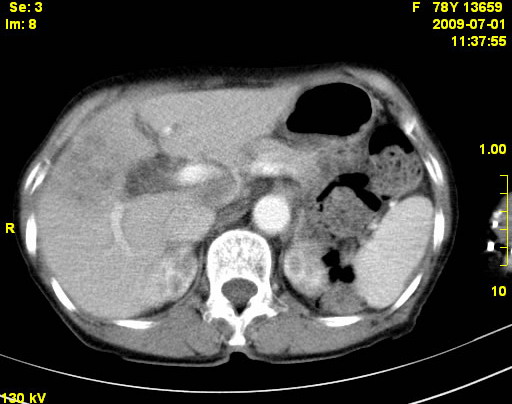

以下是引用zjzjr在2009-7-3 11:02:00的发言:[br]动脉期不均匀强化,门脉期及延迟期强化明显,肝门部见肿大淋巴结影,肝内胆管扩张.考虑肝右叶前段胆管细胞癌伴肝门淋巴结转移,胆内胆管扩张.慢性胆囊炎.

以下是引用dsl555在2009-7-4 10:59:00的发言:[br]考虑肝右叶前段胆管细胞癌伴肝门淋巴结转移,胆内胆管扩张.慢性胆囊炎. [br][br]支持。